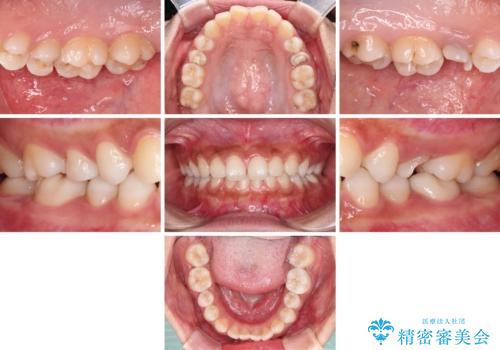

まずは虫歯を除去した上で根管治療を行い、部分矯正により骨内深い位置にまで及んだ健全な部分を引っ張り出すこととしました。

その後骨形成処置を行い、治癒を待って補綴治療を行うこととしました。

かなり深い位置にまで虫歯が及んでいたため、かなりの量を引っ張り出す必要があり、残された歯根は短く小さい状態となりました。

今後も定期的にレントゲンを撮るなど、経過を追っていく必要があります。